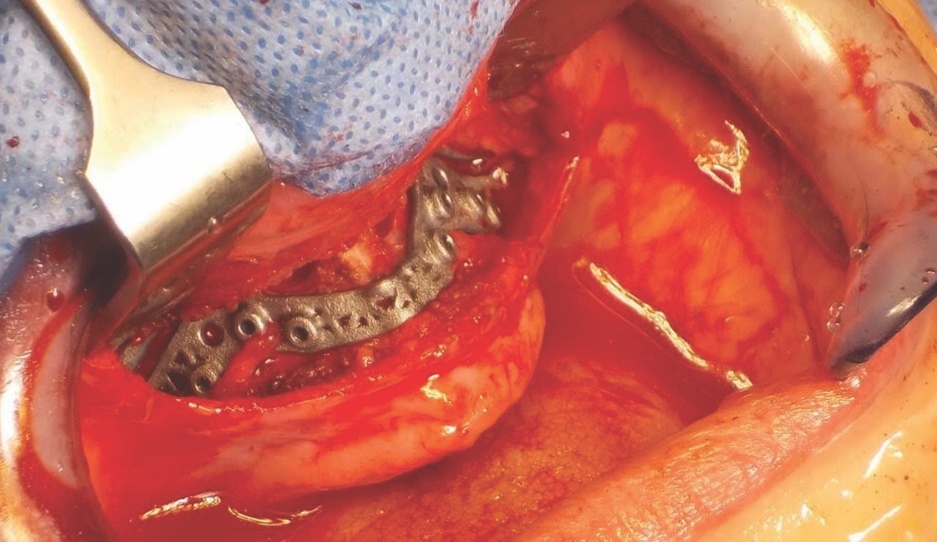

The piezoelectric system was very important in the management of this patient. It was used to split the maxillary and mandibular ridges (UR4, UR1, LL3 and LR2 regions) and also to remove the bone and open the alveolar ridge anteriorly and posteriorly on the right side of the maxilla.

Bone level fixtures were placed in the intraforaminal region with submerged healing, and axially loaded. After alveolar ridge height reduction to facilitate implant placement in the apico-coronal position, one Southern zygomatic implant (Zygex with uniabutment and healing cap) was placed in the left quadrant and three 10mm bone-level implants (021.3310) were placed (UR4, UR1 and UL1 sites) (Figure 6). Two 12mm implants (021.5310)) were then placed in the mandible (LL3, LR2 regions).